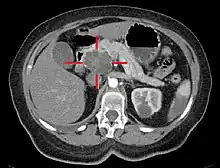

Medical imaging techniques, such as computed tomography (CT scan) and endoscopic ultrasound (EUS) are used both to confirm the diagnosis and to help decide whether the tumor can be surgically removed (its "resectability").[12] On contrast CT scan, pancreatic cancer typically shows a gradually increasing radiocontrast uptake, rather than a fast washout as seen in a normal pancreas or a delayed washout as seen in chronic pancreatitis.[56] Magnetic resonance imaging and positron emission tomography may also be used,[2] and magnetic resonance cholangiopancreatography may be useful in some cases.[32] Abdominal ultrasound is less sensitive and will miss small tumors, but can identify cancers that have spread to the liver and build-up of fluid in the peritoneal cavity (ascites).[12] It may be used for a quick and cheap first examination before other techniques.[57]

.jpg.webp)